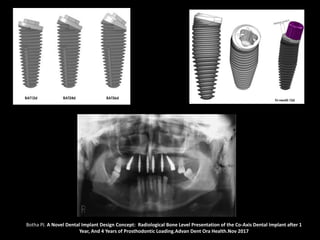

Botha PJ. A Novel Dental Implant Design Concept: Radiological Bone Level Presentation of the Co-Axis Dental Implant after 1

Year, And 4 Years of Prosthodontic Loading.Advan Dent Ora Health.Nov 2017

Botha PJ. ANovel Dental Implant Design Concept: Radiological Bone Level Presentation of the Co-Axis Dental Implant after 1 Year, And 4 Years of Prosthodontic Loading.Advan Dent Ora Health.Nov 2017